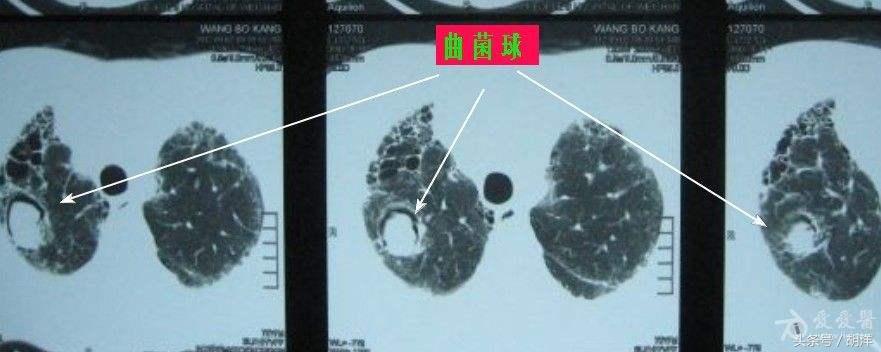

曲菌球

曲霉菌是一种常见的真菌,正常情况下,曲菌很少感染肺部结构正常,免疫力良好的人群,当肺部受到破坏,特别是形成较大空洞和支气管扩张时,曲霉菌可以趁机进入空洞扩张的支气管内与其中渗出的白细胞、纤维素等成分形成球状结构,成为曲菌球,曲菌球在空洞内能够自由的活动,对空洞壁有机械性的损伤,当损伤到管壁变异的血管瘤时,极有可能导致大出血。